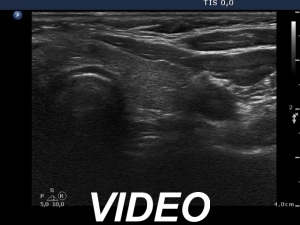

Ultrasonography. The thyroid was minimally hypoechoic and had several insignificant hypoechoic lesions. There was a solid-cystic mass dorsal to the lower pole of the right lobe.